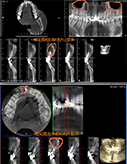

根尖囊肿切除,口腔健康如初